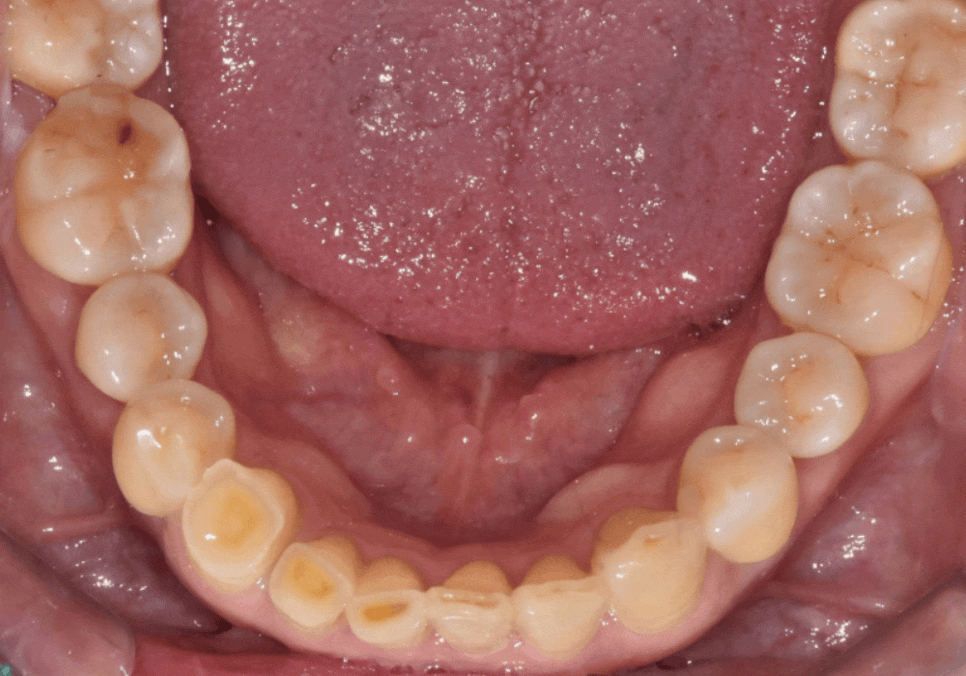

아랫니가 이미 많이 닳아

낮아진 상태라,

위 앞니 배열을 반듯하게 맞추면

특정 부위가 아랫니와 맞물리지 않고

살짝 뜨게 되는 구조였거든요.

230711

저는 이 부분을 환자분께

솔직하게 설명드렸습니다.

다행히 환자분께서도

"어금니로 잘 씹히면 되니,

이번엔 꼭 예쁜 앞니를 갖고 싶다"고

동의해주셔서

미관에 초점을 맞춘 디자인을 진행했습니다.

또한, 환자분의 씹는 힘(교합력)이 매우 강해

일반 도자기는 깨질 위험이 컸습니다.

230215

그래서 강도가 월등히 높은

'지르코니아'를 선택해

튼튼함까지 놓치지 않았습니다.